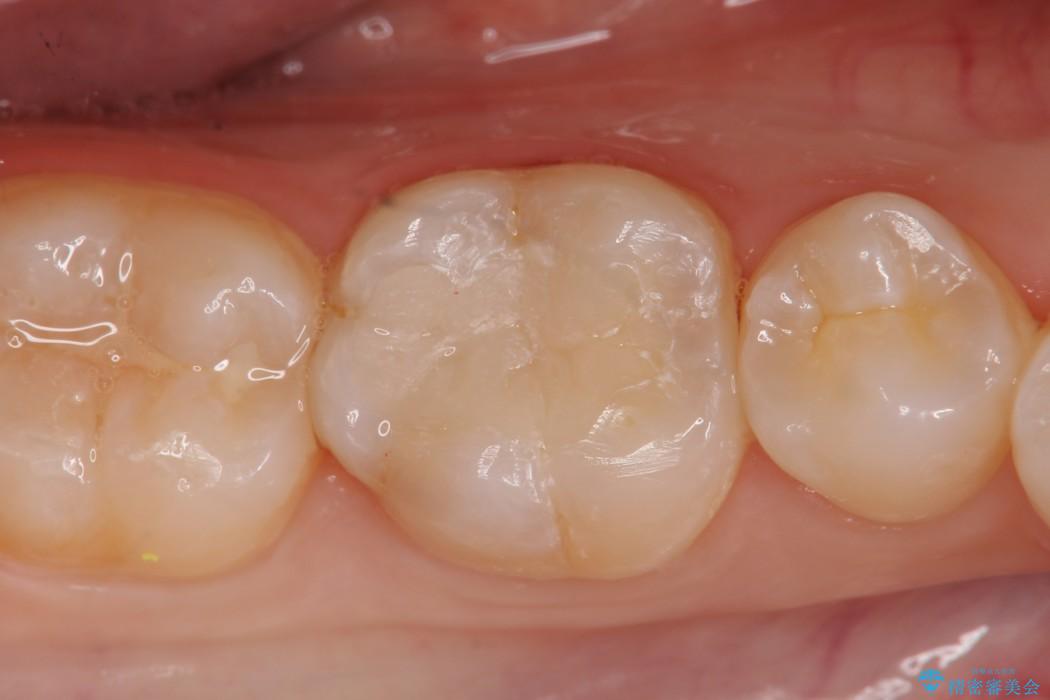

診査をした結果、顎左右の前から6番目の歯に深い虫歯があったため、詰め物(インレー)タイプで修復していく(e-max プレスインレー)での治療を行いました。

早めの治療を行えたことにより詰め物での治療にて治すことができました。